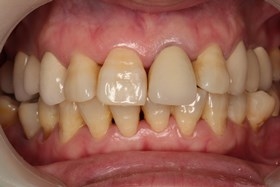

- 治療前全口X光片、口內正面照片。

治療前全口X光片、口內正面照片